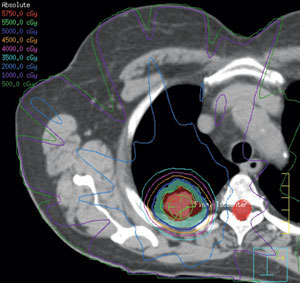

בעבר, מטופלים עם מחלות רקע קשות שהיוו סיכון הרדמתי גבוה (Medically inoperable), טופלו בקרינה חיצונית (External beam radiotherapy), במינון 44-66 גריי (Gy) במקטעים שגרתיים, לאורך כשישה שבועות. התוצאות היו הישרדות כוללת לחמש שנים של 10 עד 30 אחוזים בלבד, בהשוואה ליותר מ־60 אחוזים בחולים שנותחו.

התקדמות טכנולוגית ומחקרית מאפשרת מתן טיפול קרינתי במנות גבוהות ובמקטעים בודדים ישירות לגידול, ללא פגיעה באיברים סמוכים. הטיפול, הנקרא טיפול קרינה סטראוטקטי (SBRT ,Stereotactic Body Radiation Therapy), נבדק במחקר 0236 RTOG, שם ניתן מינון של 54 גריי בשלושה מקטעים בלבד. התוצאות הראו שליטה מקומית של מעל 90 אחוזים והישרדות תלוית-סרטן בשיעור דומה לחולים שנותחו[4].